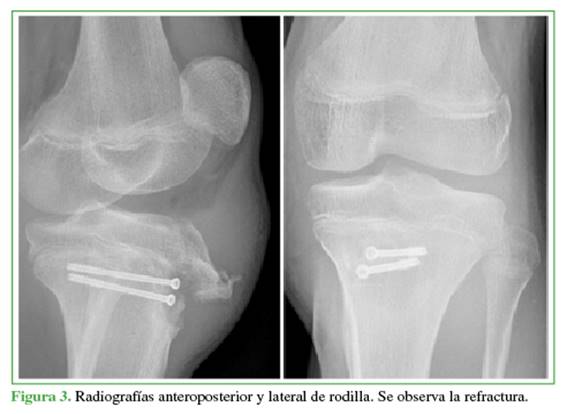

A los 4 meses, acudió nuevamente por dolor e impotencia funcional en la rodilla izquierda tras una hiperextensión. Tenía derrame articular, rótula ascendida y dolor en la TTA. En la radiografía, se observaba una fractura-arrancamiento de la TTA tipo IIB de Ogden. En una tomografía computarizada, se descartó el compromiso intrarticular y se confirmó la consolidación del trazo posterior de la fractura inicial (Figuras 3 y 4).